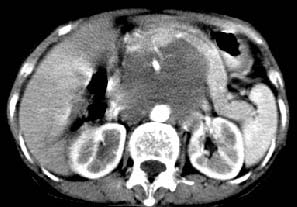

我的第1诊断还是考虑是淋巴类病变1}。从病灶形态上看不是很规则,但其更向是多个结节的融和,其内有少许坏死,整个病灶的强化不是很明显,临近左恻肠间隔有增厚,2}我认为更重要的一点的是肠系膜有明显增厚呈片状。3}患者的脾脏不大其未见异常病灶。结合以上几点我首先考虑是转移性{但对此诊断我觉得不足之处;转移性的淋巴结肿大融合为什么没有坏死?}。{另外患者无大便习惯改变及血便,其发现右颈包块在今年过年无意发现}。以上是我的浅分析望各位战友继续讨论!谢谢!!

实话实说,不认识,看什么都象!!我怎么感觉左侧肠管分布及形态那么不舒服呀?病史也有些短,会不会是腹膜后脓肿呀!不好意思,猜的,向大家学习来了!呵呵

影象表现:平扫,首先可见胃壁明显增厚,内外边缘清晰,外缘光滑,内边缘不归整,同时胃腔明显缩小。

再看从肠系膜根部到胰腺后主动脉及上腔静脉周围可见相连的较大的软组织肿块影,形态不规则,呈明显

的大小不等的分叶状,其中密度较均匀但其中可见条状低密度区,肿块边缘比较清晰周围的小肠受压移位

明显且堆积。

影象诊断:考虑淋巴瘤待除外胃癌腹膜后淋巴结转移

讨论:首先看肠系膜和腹膜后的肿块我认为是多发融合的肿大的淋巴结。理由1大小不等的分叶,分布比较

自由。2其中的包绕的血管和周围少量的脂肪即所说的。

同时胃的影象表现和临床的不典型表现,所以我认为淋巴瘤,临床表现不支持胃癌